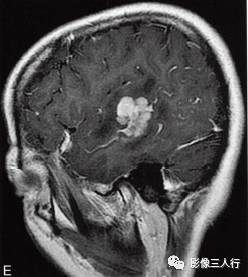

图1右颞叶横纹肌样脑膜瘤

A.T1WI横断面;B、C.T2WI横断面;D、E、F、G.增强横断面、矢状面、冠状面;H.HE×100

图1A:MRI T1WI示,右侧颞叶不规则形肿块,信号欠均匀,为稍低信号与小斑片状稍高信号混杂。其累及颞叶灰白质,界限欠清、边缘不整,大小约4.1cm×4.3cm×5.1cm。邻近脑沟脑裂变浅变平,周边脑实质受压。图1B、C:T2WI示,右颞不规则形肿块,信号欠均匀,为稍高信号与小斑片状略低信号混杂。灶周见带状高信号脑水肿。图1D~G:T1WI C示,右侧颞叶肿块呈不均匀的多个结节块状明显强化,邻近脑膜为线条状强化、增厚。